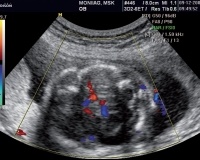

На современном этапе развития ультразвуковой диагностики в большинстве случаев шизэнцефалия диагностируется пренатально при плановом обследовании на беременность. Закрытая щель гораздо лучше визуализируется, а открытая шизэнцефалия может остаться незамеченной. Для послеродового подтверждения диагноза детскому неврологу необходимы следующие методы исследования:

• Нейросонография. Ультразвук головного мозга применяется как альтернатива магнитно-резонансной томографии у новорожденных, младенцев до закрытия большого родничка. Ультразвук очень информативен при шизэнцефалии I. Метод также используется для выявления сопутствующих нарушений в структуре структур головного мозга. Для уточнения диагноза к нейросонографии добавляют УЗИ сосудов головного мозга.